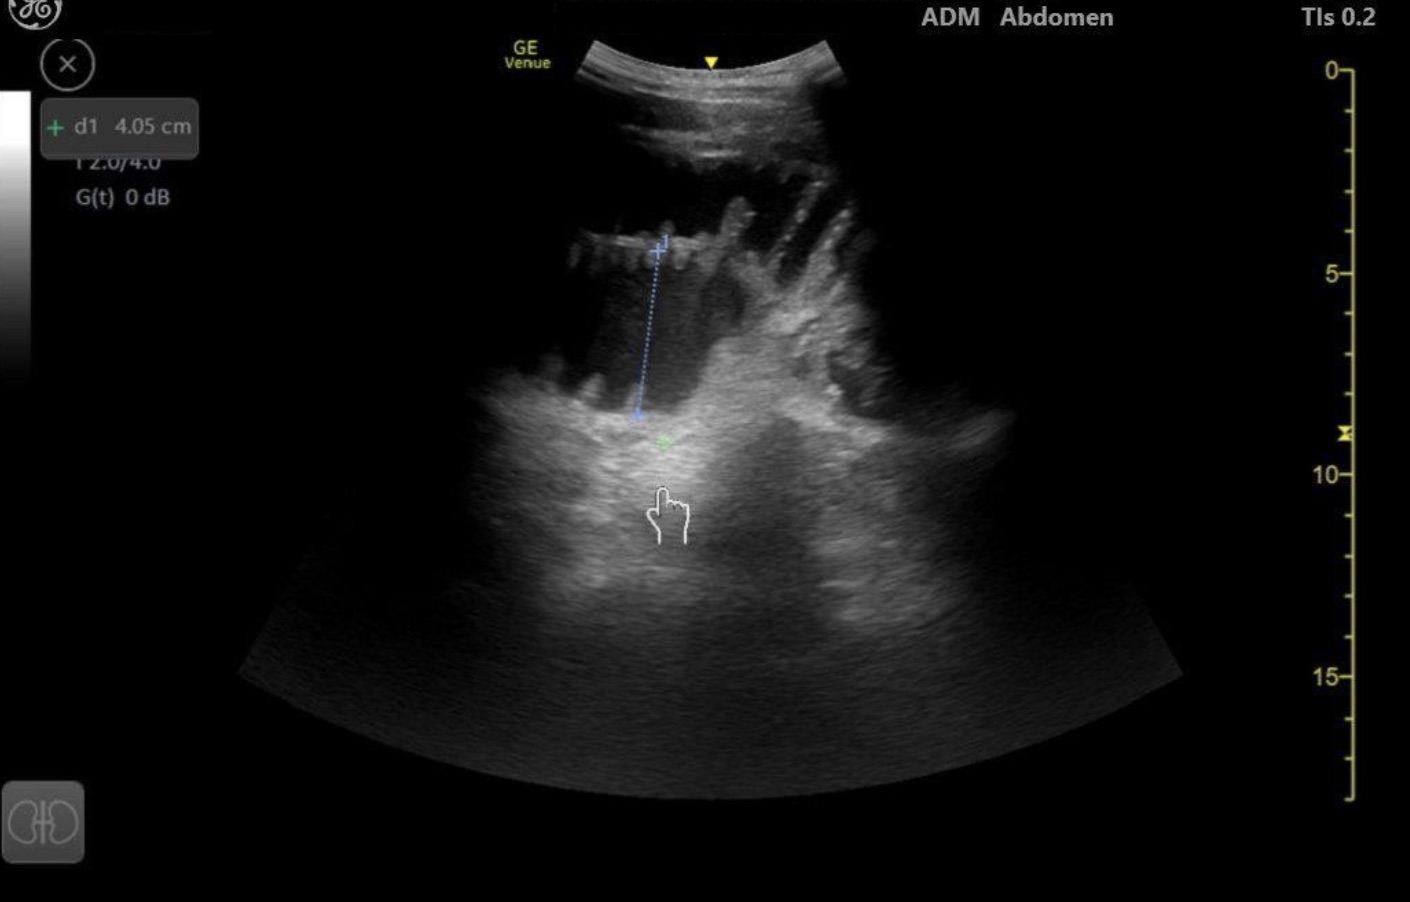

Small Bowel Obstruction

Brief narrative description of case

75 year old male with PMH of HTN, HLD presenting with concern of right sided abdominal pain for 3 days, progressively worsening. He appears uncomfortable and is tachycardic on arrival. The goals for this case are to recognize the differential diagnosis and the role of using bedside POCUS to diagnose and expedite care.